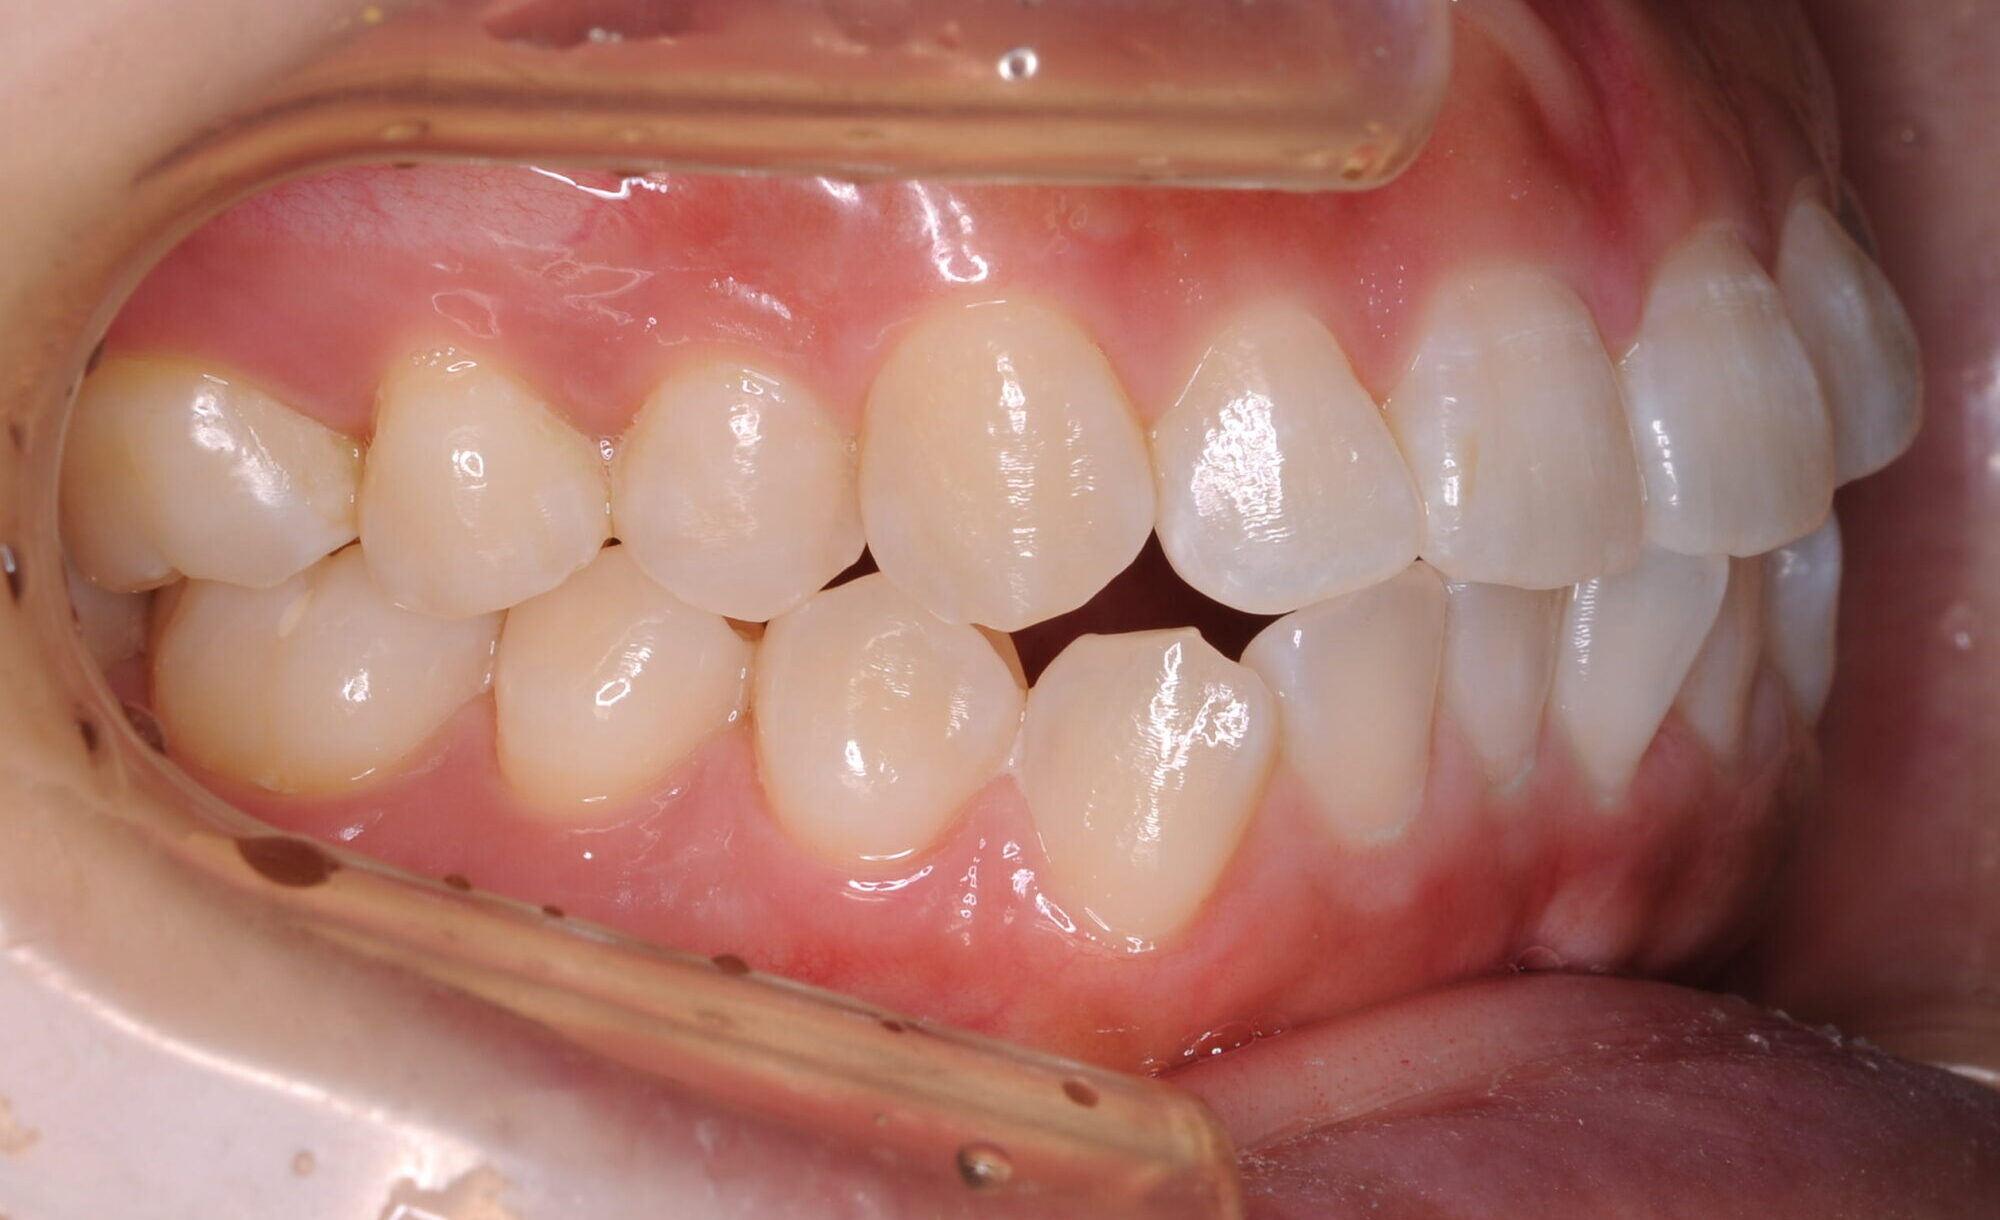

症例写真 after